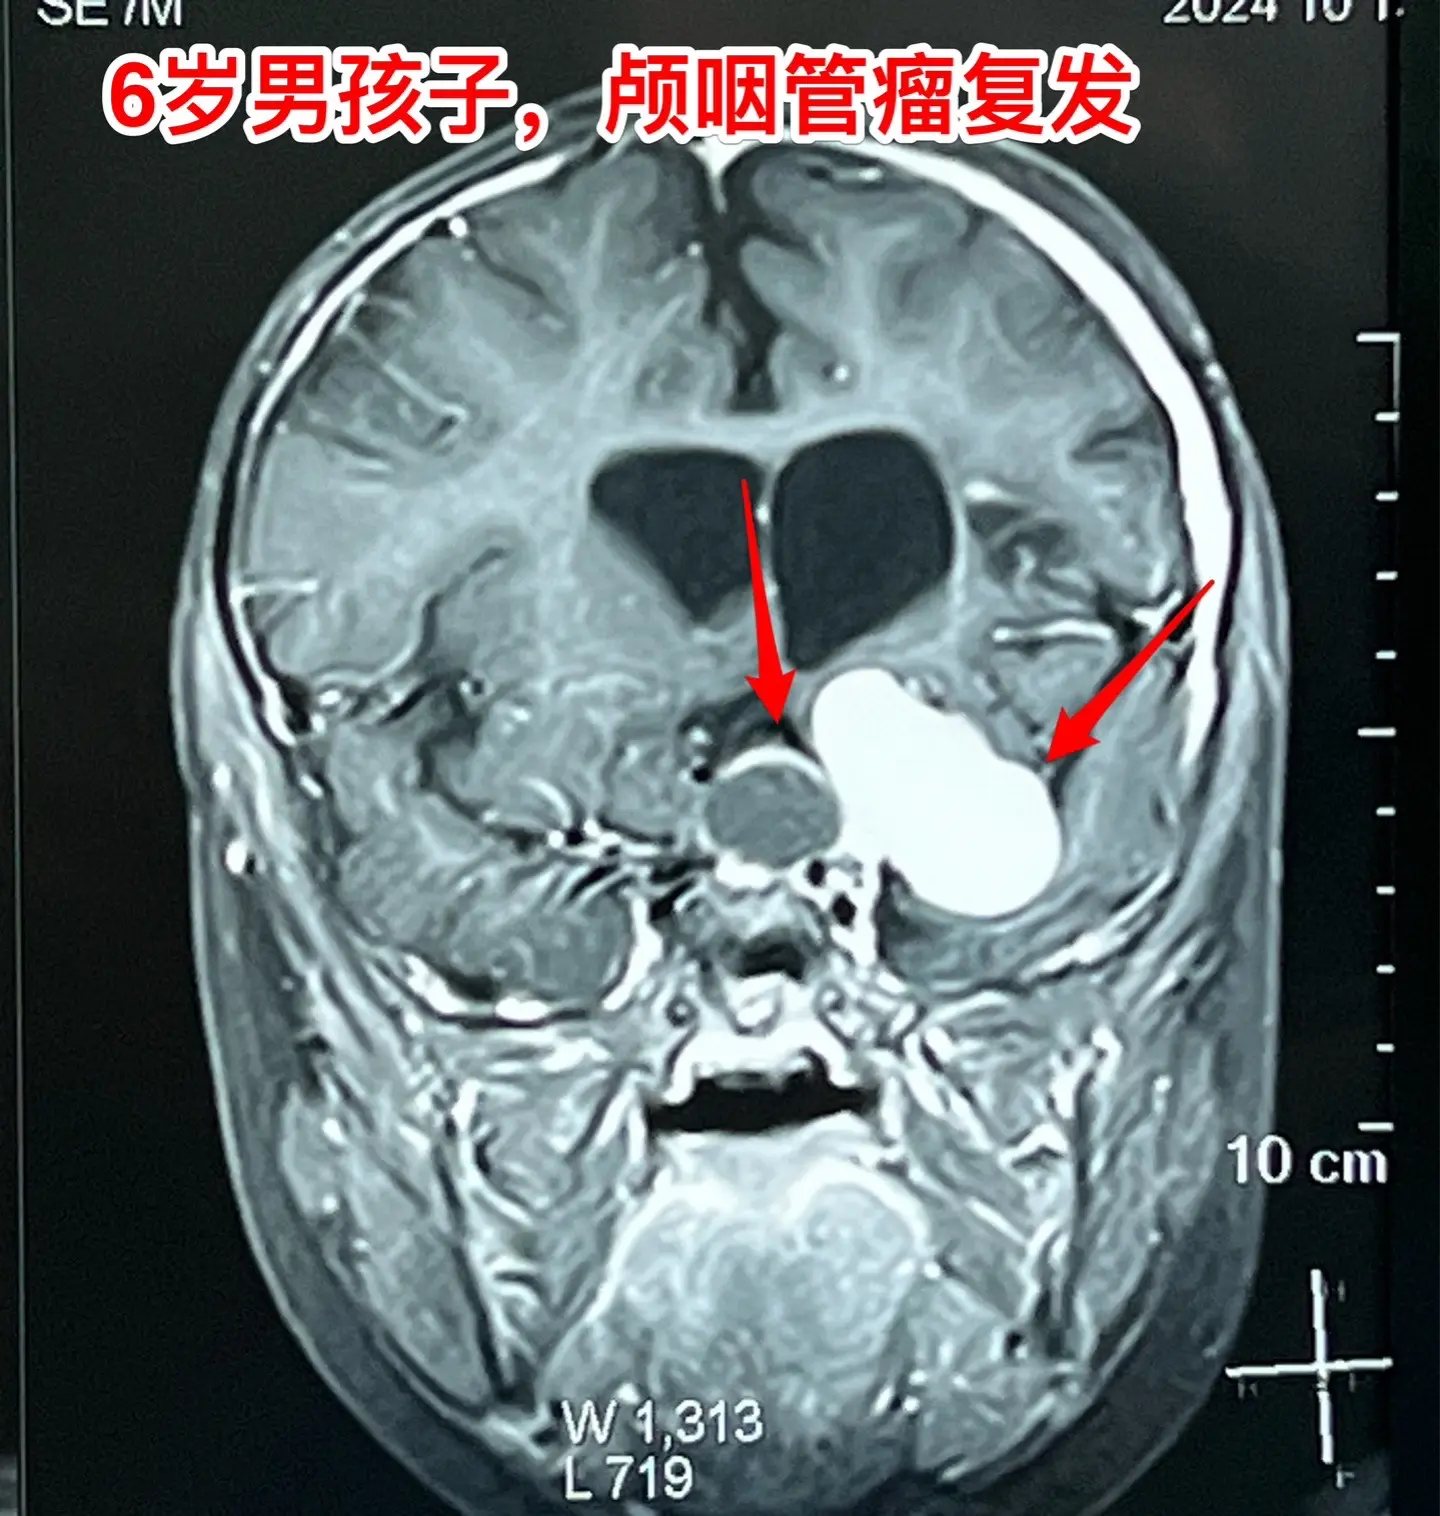

今日两个颅咽管瘤手术。1,6岁男孩子,安徽宿州人。2023年5月因视力下降发现了脑部长了巨大颅咽管瘤,见图1。家长曾经通过微信找我看过,最终选择在上海某医院行手术治疗,手术后出现右侧偏瘫,经过康复治疗后能勉强走路,但是右手还不能拿笔写字。2023.12磁共振就显示颅咽管瘤复发了(多块肿瘤复发)。2024.10又出现视力下降,故来找我作手术。今天手术中发现有四块较大的肿瘤,同时有很多个小钙化。所见肿瘤均顺利切除了。对比两次手术前的磁共振,可以说第一次手术更容易达到完全切除肿瘤,很遗憾,那一次机会错过了。 2,9岁男孩子,江苏盐城市的。因头痛、呕吐检查发现脑部有典型的颅咽管瘤,伴有脑积水。病人到我科住院后经用甘露醇和地塞米松后头痛、呕吐症状消失,能正常吃喝。今日作了开颅手术,顺利切除肿瘤。